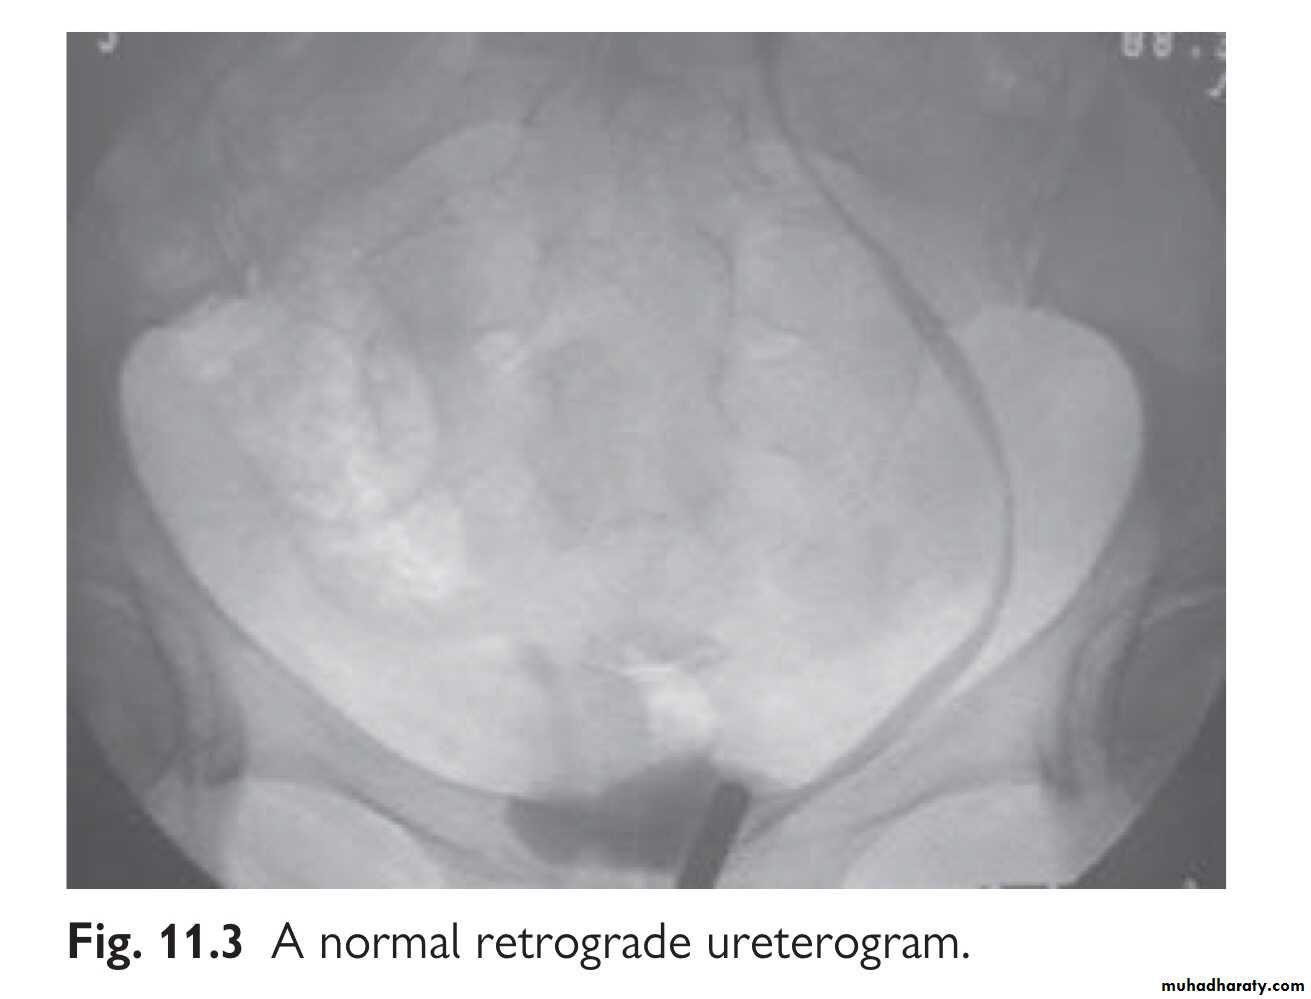

IVU or retrograde ureterogram. Ultrasonography may demonstrate hydronephrosis, but hydronephrosis may be absent when urine is leaking from a transected ureter into the retroperitoneum or peri- toneal cavity. The IVU usually shows an obstructed ureter or occasionally, a contrast leak from the site of injury.